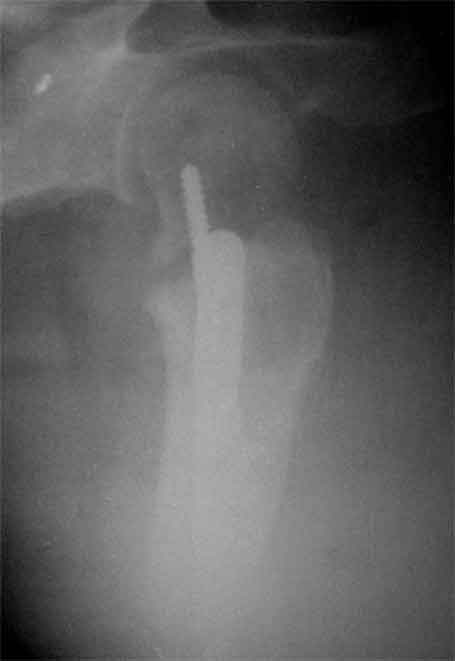

Доброго время суток, коллеги. Обратилась на консультацию пациентка 52 лет. травма и первичный остеосинтез перелома бедра около года назад, далее был обнаружен перелом шейки бедра (возможно ятрогенный), реостеосинтез реконструкционным гвоздем 8 месяцев назад. Конченость не опорна. В больнице, где выполнялись эти вмешательства предложили выполнить THR с длинной ножкой. Возможно ли в такой ситуации добиться сращения шейки при помощи каких-либо остеотомий?

возраст как раз далеко не преклонный, да и головка выглядит "живой"

На мой взгляд дистальный перелом срощен, а состояние тазобедренного сустава и молодой возраст пациентки позволяют произвести вальгизирующую остеотомию проксимального бедра. В случае, если нет сращения дистального перелома можно фиксировать длинным DHS; Если есть сращение- обычным DHS.

Коллкега на представленных снимках имеется ротационная стабильность и плохо репонированный перелом. В данный момент думать об эндопротезтровании или межвертельной остеотомий рано, так как перелом диафиза бера еще полностью не сросся, я думаю, надо на данном этапе попытаться стабилизировать перелом шейки бедра конюлированными винтами, удалить проксимальный винт, попытатся сделать репозицию, хотя маловероятно, что получется добиться улучшения, и стабилизировать 3 конюлированными винтами и дать компресию, таким образом дать шанс, может перелом срастется до удаления штифта. Удачи

Применение одного импланта для лечения ипсилатеральных переломов резко ограничено из-за риска осложнениий, связанных с применением неадекватной фиксации. По литературным данным, осложнения после применения зарекламированных реконструктивных гвоздей для лечения ипсилатеральных переломов доходили до 56%.

Несостоятельность фиксации шейки не давала возможности срастись перелому, потому что запланированнная динамическая нагрузка в большинстве случаев прекращалалась из-за вторичного варусного смещения шейки.

В данном случае навряд ли можно ожидать образования сращения на бедре и еще имеется укорочение засчет варуса.

поможет установит сращение на шейке и бедре. Восстановление длины можно сделать за счет вальгусной остеотомии оригинальным методом Blade Plate. На бедро шт ифт ретроградно или пластина, кому что нравится. На мой взгляд, еще имеется шанс спасти головку остеотомией.